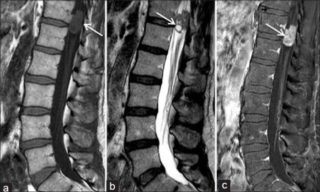

Гемангиома

Гемангиома — опухоль, состоящая из близко расположенных сосудов

Гемангиома – большое скопление кровеносных сосудов, которое характеризуется быстрым разрастанием за короткий период времени. Носит разрушительный характер, нередко травмирует здоровые сосуды и ткани. Бывает разных размеров, часто болезненна. Отличается ярким цветом. Существующие разновидности: простая, кавернозная, сенильная, комбинированная, капиллярная. Новообразование может перерастать в злокачественную опухоль.

Гемангиома – это доброкачественное уплотнение на спине под кожей возле позвоночника, которое формируется из сосудов.

Появиться шишка может, если долго находиться под солнцем, но однозначно все версии сходятся на том, что большую роль играет наследственность.

Для гемангиом характерно бессимптомное течение. Очень редко имеется болезненность. Еще реже может разрушиться позвонок в месте локализации новообразования.

Если размер шишки большой, то нужно принимать меры. Лечение основывается на чрескожной пункционной вертебропластике. Анестезия местная. Во время операции в патологическое место вводят особый состав. Он застывает и оказывает разрушительное воздействие на опухоль. Процедура безболезненна, нет крови и нарушения целостности кожных покровов.